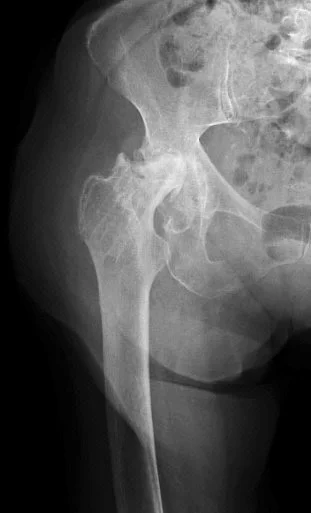

Radiological Evaluation

- Radiological evaluation

- AP and ?Lateral (cross-table)